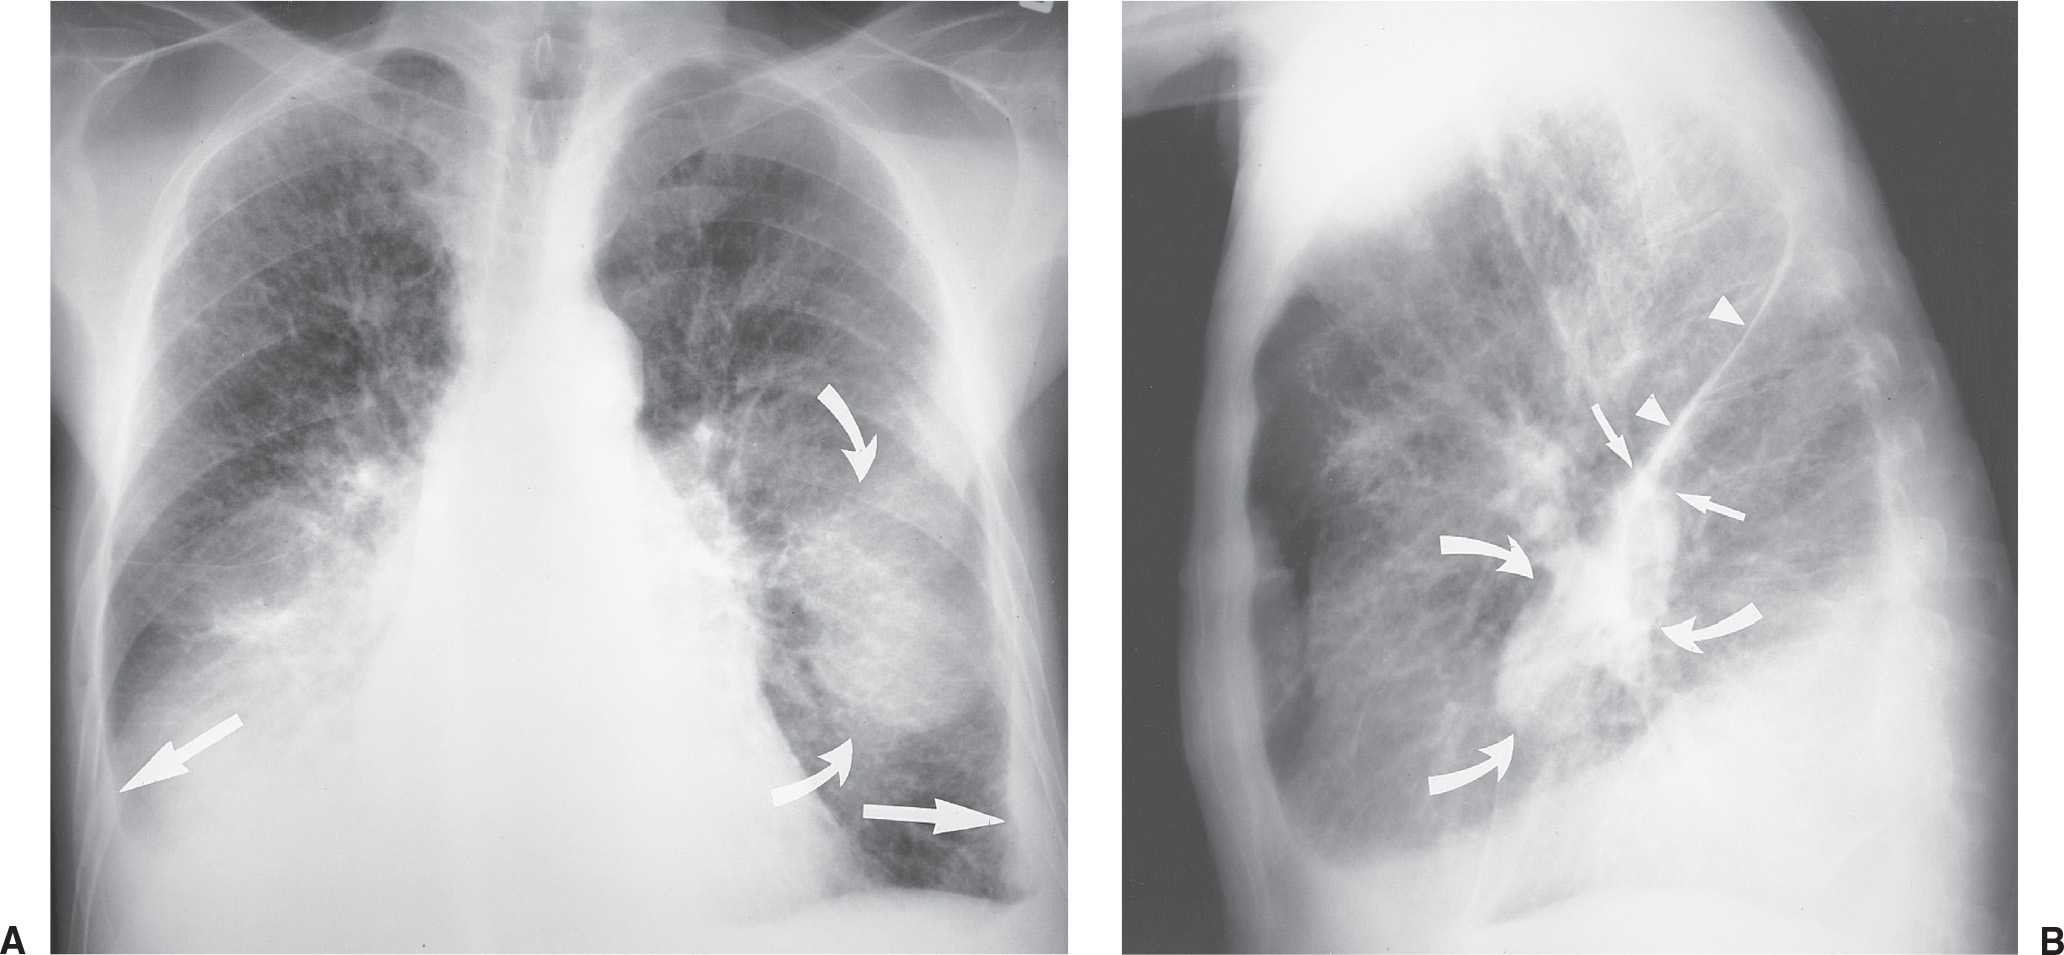

Симптомы и причины скопления воды в легких